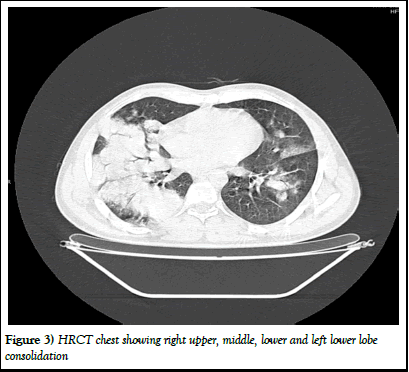

He was given IV antibiotics and tablet oseltamivir and later he developed progressive breathlessness, saturation on room air was 62% and 92% on 10 L oxygen through non re-breathable mask. ABG was sent showing severe ARDS with type 1 respiratory failure. HRCT chest done showing bilateral lower lobe, middle lobe and right upper lobe pneumonia. He was put on NIV with ARDS protocol and he was maintaining saturation, work of breathing on NIV. RTPCR for COVID-19 and H1N1 was sent and which was negative.

Figure 3) HRCT chest showing right upper, middle, lower and left lower lobe consolidation